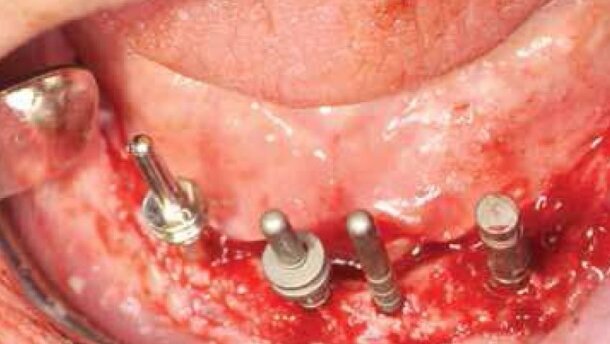

W kolejnym etapie przygotowano łoża implantów w odcinku przednim (Ryc. 9) oraz wszczepiono implanty okolicy zębów 31, 41, 42 i 43 Straumann® NNC, SLActive® 12 mm, TiZr (Ryc. 10-12). W odcinku przednim zdecydowano o zastosowaniu w/w implantów ze względu na wąski wyrostek zębodołowy przy jednoczesnym zachowaniu ich bardzo dużej wytrzymałości mechanicznej. Implanty NNC wykonane ze stopu tytanowo-cyrkonowego znanego pod nazwą Roxolid® mimo średnicy 3,3 mm posiadają wytrzymałość większą od implantów standardowych o średnicy 4.1 mm.

Warunki anatomiczne okolicy zęba 33 pozwoliły na wszczepienie implantu standardowego, czyli Straumann® SP, Ø 4.1mm RN, SLActive® 12 mm.

Implanty zamknięto śrubami zamykającymi, a ranę zaopatrzono szwami 5.0 (Ryc. 13) oraz wykonano kontrolne zdjęcie pantomograficzne (Ryc. 14).